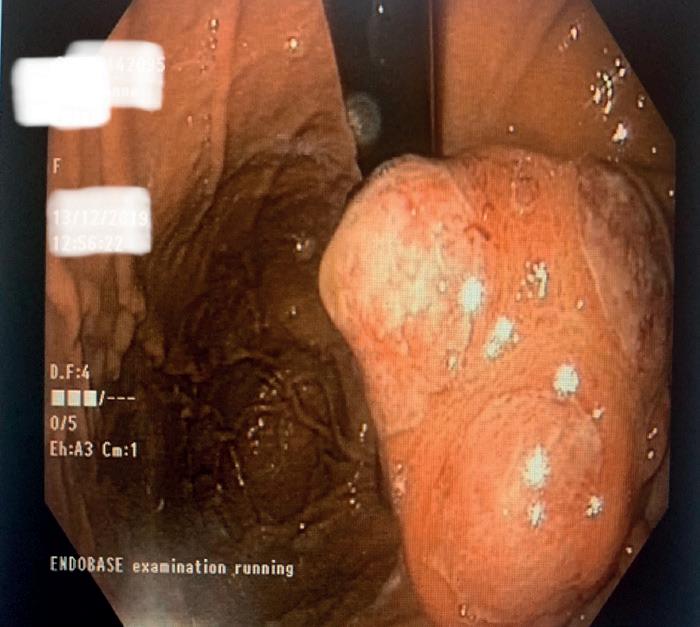

Behandlingen med atezo+bev fikk FDA-godkjenning 29. mai 2020 og EMA-godkjenning 2. november samme år, og allerede 15. februar året etter besluttet Beslutningsforum at immunterapi kunne innføres for norske pasienter med leverkreft. Vi feiret denne dagen med bløtkake på vår avdeling, og en måned senere ga vi vår første pasient denne behandlingen [Figur 3].

Innføringen av immunterapi ved HCC er nærmest et glansbilde tatt i betraktning de mange etterlengtede behandlinger som kommer sent eller aldri til Norge. Veien til ny, mer effektiv behandling er å delta i studier av nye medikamenter og behandlingskombinasjoner, og vi har selv bidratt i en lang rekke av de store studiene, for eksempel i utprøvningen av immunterapi i form av pembrolizumab (en PD-1-hemmer) i andre linje etter